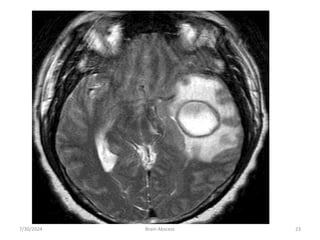

• MRI :

• T1 :

• necrotic center ( hypointense)

• Capsule ( hyperintence)

• Edema ( hypointence)

• T2 :

• necrotic center ( hyperintence)

• Capsule ( hypointence)

• Edema ( hyperintence

7/30/2024 Brain Abscess 18